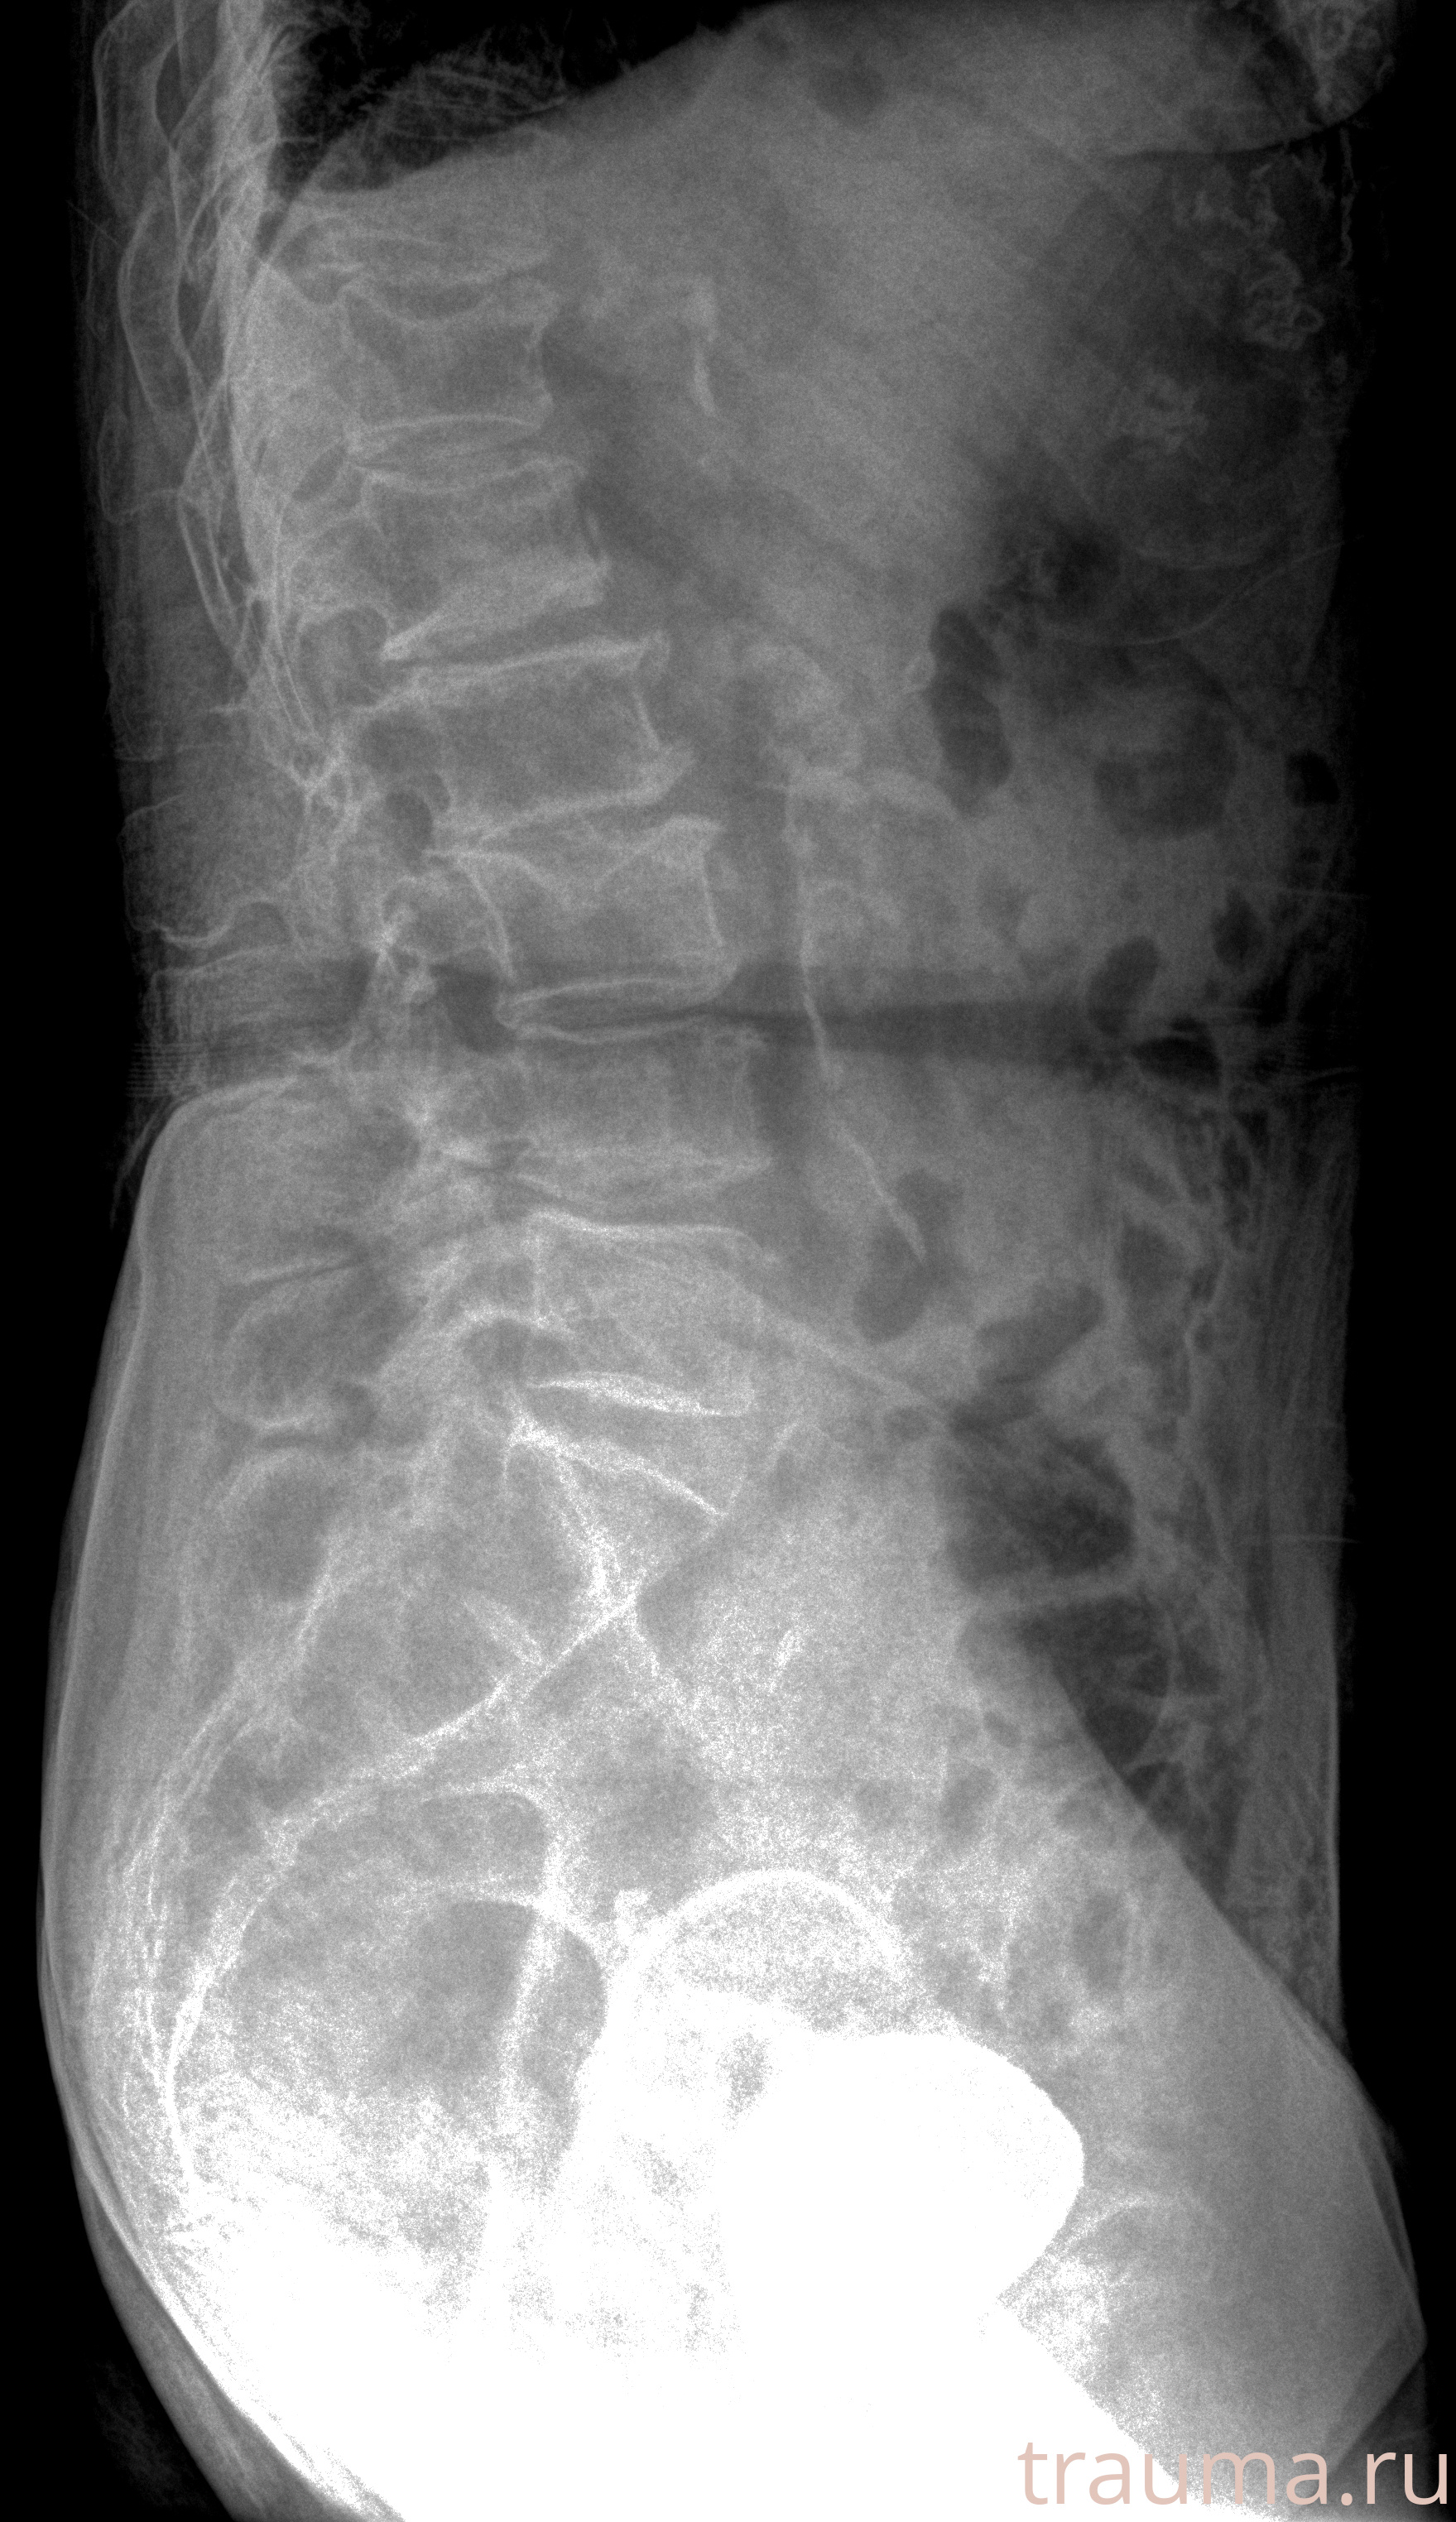

Рентгенограммы

Рентген на дому: по вашему адресу приезжает врач-рентгенолог, травматолог-ортопед с мобильным рентгеновским аппаратом, проводит диагностику травмы или заболевания, делает необходимые рентгенограммы, дает рекомендации по дальнейшему лечению. Получить качественные снимки в домашних условиях возможно благодаря уникальной методике, разработанной МосРентген Центром для института  Склифосовского